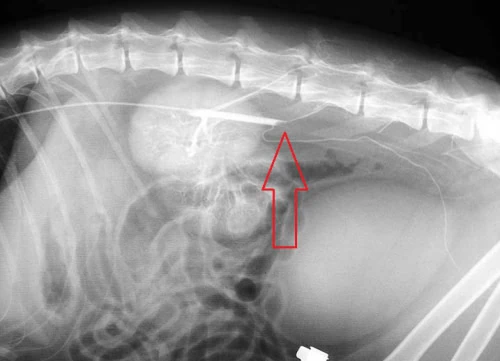

下の写真は筆者の経験した、若い猫で生じた原因のはっきりしない特発性腹部大動脈血栓塞栓症での血管造影の写真です。赤矢印の先に白く見える造影剤血栓によって欠けている部分がありますが、これはそれ以下への血行が完全に遮断されていることを示しています。腹部大動脈血栓塞栓症とはどういうものかということをご理解する上でのご参考としてご覧ください。

この写真の猫は心疾患や大きな合併症がみられなかっため、外科的血栓を摘出して無事に回復しました。その後再発はなく、約7年後に悪性腫瘍リンパ腫で生涯を全うするまでまで問題ない生活を送ることができています。ただし、血栓形成の原因となる心疾患などの予後の悪い病気を伴わず、外科手術が功を奏するケースは稀なものでしかありません。